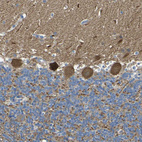

Immunohistochemical staining of human gastrointestinal shows strong granular cytoplasmic positivity in glandular cells.